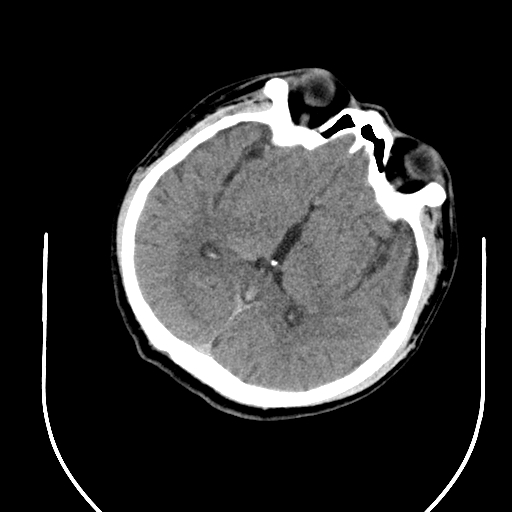

入院头CT

急诊予以静脉溶栓,同时完善头颈CTA+CTP、MIStar相关检查

结合CTA结果,提示左侧颈内动脉起始部至颈内动脉末端未见显影,起始部成鼠尾征改变,前交通动脉开放,双侧大脑中动脉显影良好。MIStar图像提示核心梗死灶和缺血半暗带较小,但是MTT提示左侧大脑中动脉流域区明显延长。

考虑此次发病可能为左侧颈内动脉慢性狭窄基础上出现急性闭塞,导致左侧大脑半球血流量受影响,幸运的是前交通动脉开放,受到对侧代偿供血,左侧大脑半球未出现急性大面积缺血,向患者家属交代后,家属同意暂静脉溶栓观察。

静脉溶栓过程患者症状逐渐减轻,构音障碍和右侧肢体活动不灵均有缓解,NIHSS评分降到2分。就在溶栓快结束时,患者突然症状再次加重,NIHSS评分10分,复查头CT未见出血。结合之前影像,不除外左侧颈内动脉急性闭塞形成血栓后脱落可能,立即启动急诊介入治疗。